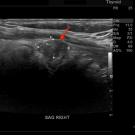

A 71-year-old man presented for evaluation of a thyroid nodule that had been found incidentally on carotid ultrasound and magnetic resonance imaging of the brain.